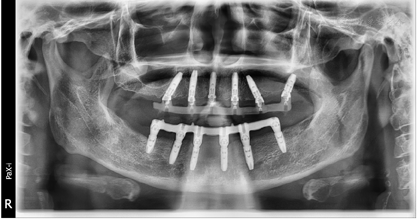

术后一年随访:拍摄全景片显示种植体周围骨结合良好,边缘骨高度稳定(图19)。义齿外形无变化,下颌义齿前牙区舌侧面见牙结石。

治疗计划:(1)口腔卫生宣教,指导患者正确刷牙以及使用冲牙器进行日常维护与清洁;嘱患者定期洁牙(6个月)及定期复查(12个月)。(2)取下上下颌义齿,清洁复合基台及义齿组织面,抛光义齿组织面,重新戴入上下颌义齿。(3)电子面弓检查患者咬合状况:结果显示患者双侧咬合平衡,咬合功能正常(图20)。(4)双色法检查患者口内咬合情况:双侧咬合接触均匀,前牙有引导。